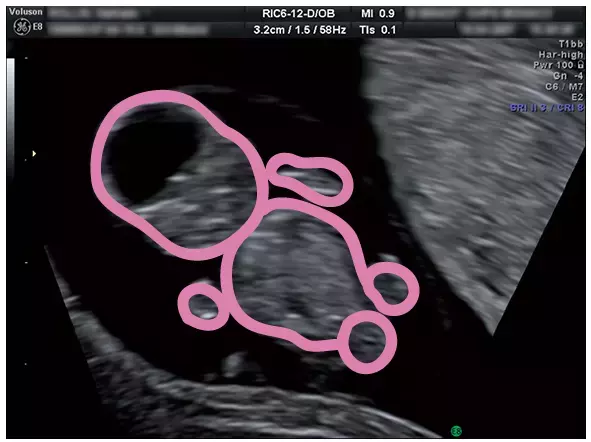

妊娠9週のエコー写真

3頭身になり、体を動かす様子も

さらに体の輪かくがはっきりし、頭、胴体、手、足の区別がつくようになります。

指まで見える場合もあり、タイミングがよければ、手や足をバタバタさせたり、体を伸ばしたり曲げたりする様子も見られ、愛しい気持ちがわき上がるでしょう。心臓や脳など人間の基本的な臓器の原型がほぼ出来上がる時期です。

妊娠3ヶ月のエコー(超音波)写真

この頃は手足をそろえて前に出す姿勢が多いので、まるで手をグーにしているよう。